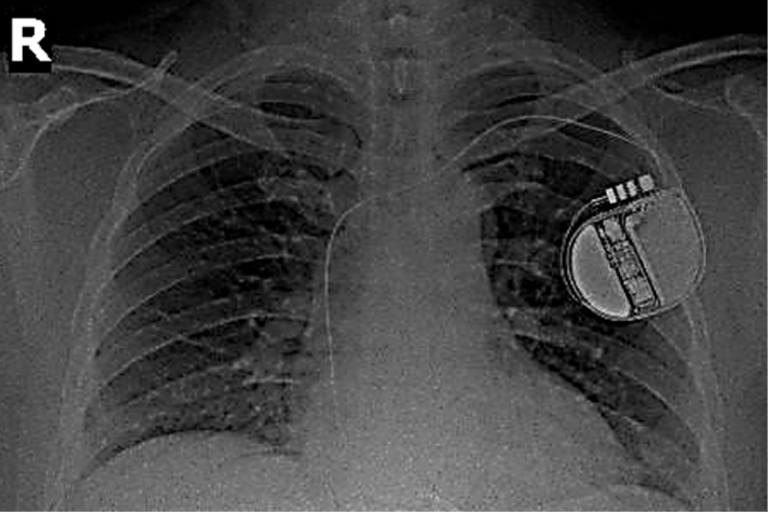

Thoát khỏi tử thần nhờ thiết bị phá rung tim cấy ghép trong cơ thể

Nhờ thiết bị phá rung tim cấy ghép trong cơ thể, nam bệnh nhân đã thoát khỏi nguy cơ ngưng tim thêm một lần nữa sau cơn choáng váng đột ngột.